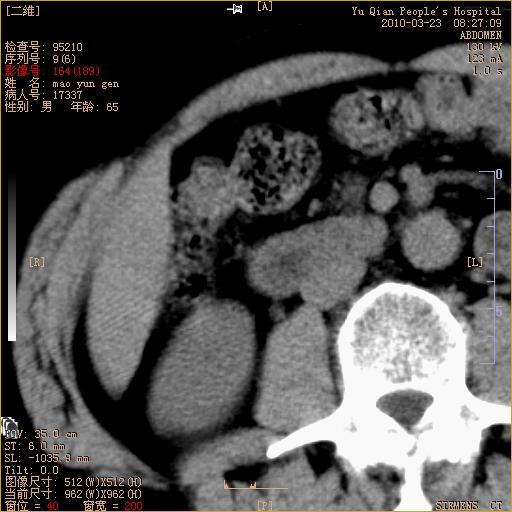

标题: CT25266:消瘦月余,前来肝部检查,请看看肠腔 [打印本页]

标题: CT25266:消瘦月余,前来肝部检查,请看看肠腔

肝区结肠占位,腺癌可考虑,建议肠镜活检。

升结肠肠壁增厚,不均强化,考虑升结肠腺癌可能性,建议肠镜检查。

1)考虑升结肠癌。2)右肾小囊肿。